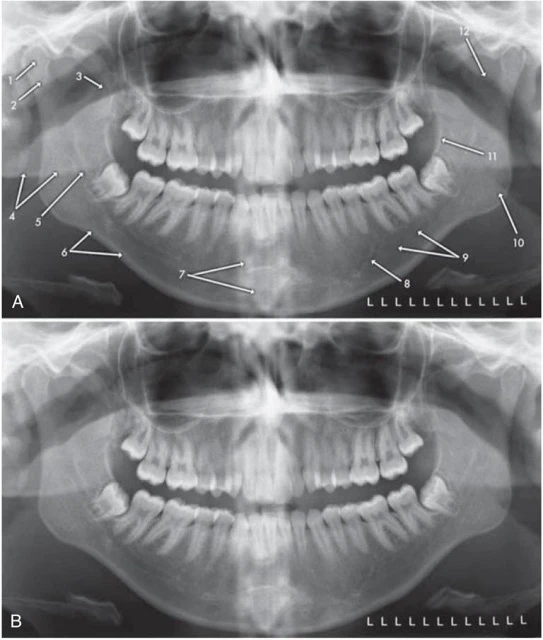

Hình 17. Cấu trúc giải phẫu xương hàm dưới trên hình ảnh phim x-quang toàn cảnh. Hình ảnh A và B là hai hình trùng lặp của cùng một bệnh nhân. 1, Lồi cầu xương hàm dưới. 2, Cổ lồi cầu xương hàm dưới. 3, Mõm vẹt xương hàm dưới. 4, Hình ảnh ma, mặt sau của bờ dưới hàm dưới bên trái. 5, Ống thần kinh xương ổ răng dưới. 6, Bờ dưới xương hàm dưới. 7, Hình chồng lên của bóng đốt sống cổ. 8, Lỗ cằm. 9, Hõm dưới hàm (chỗ lõm tại vị trí tuyến nước bọt lưỡi). 10, Góc hàm. 11, Gờ chéo ngoài. 12. Hõm xích ma.